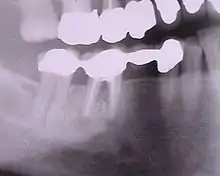

Radiographie des six implants

Contrôle de la cicatrisation à une semaine de l'intervention